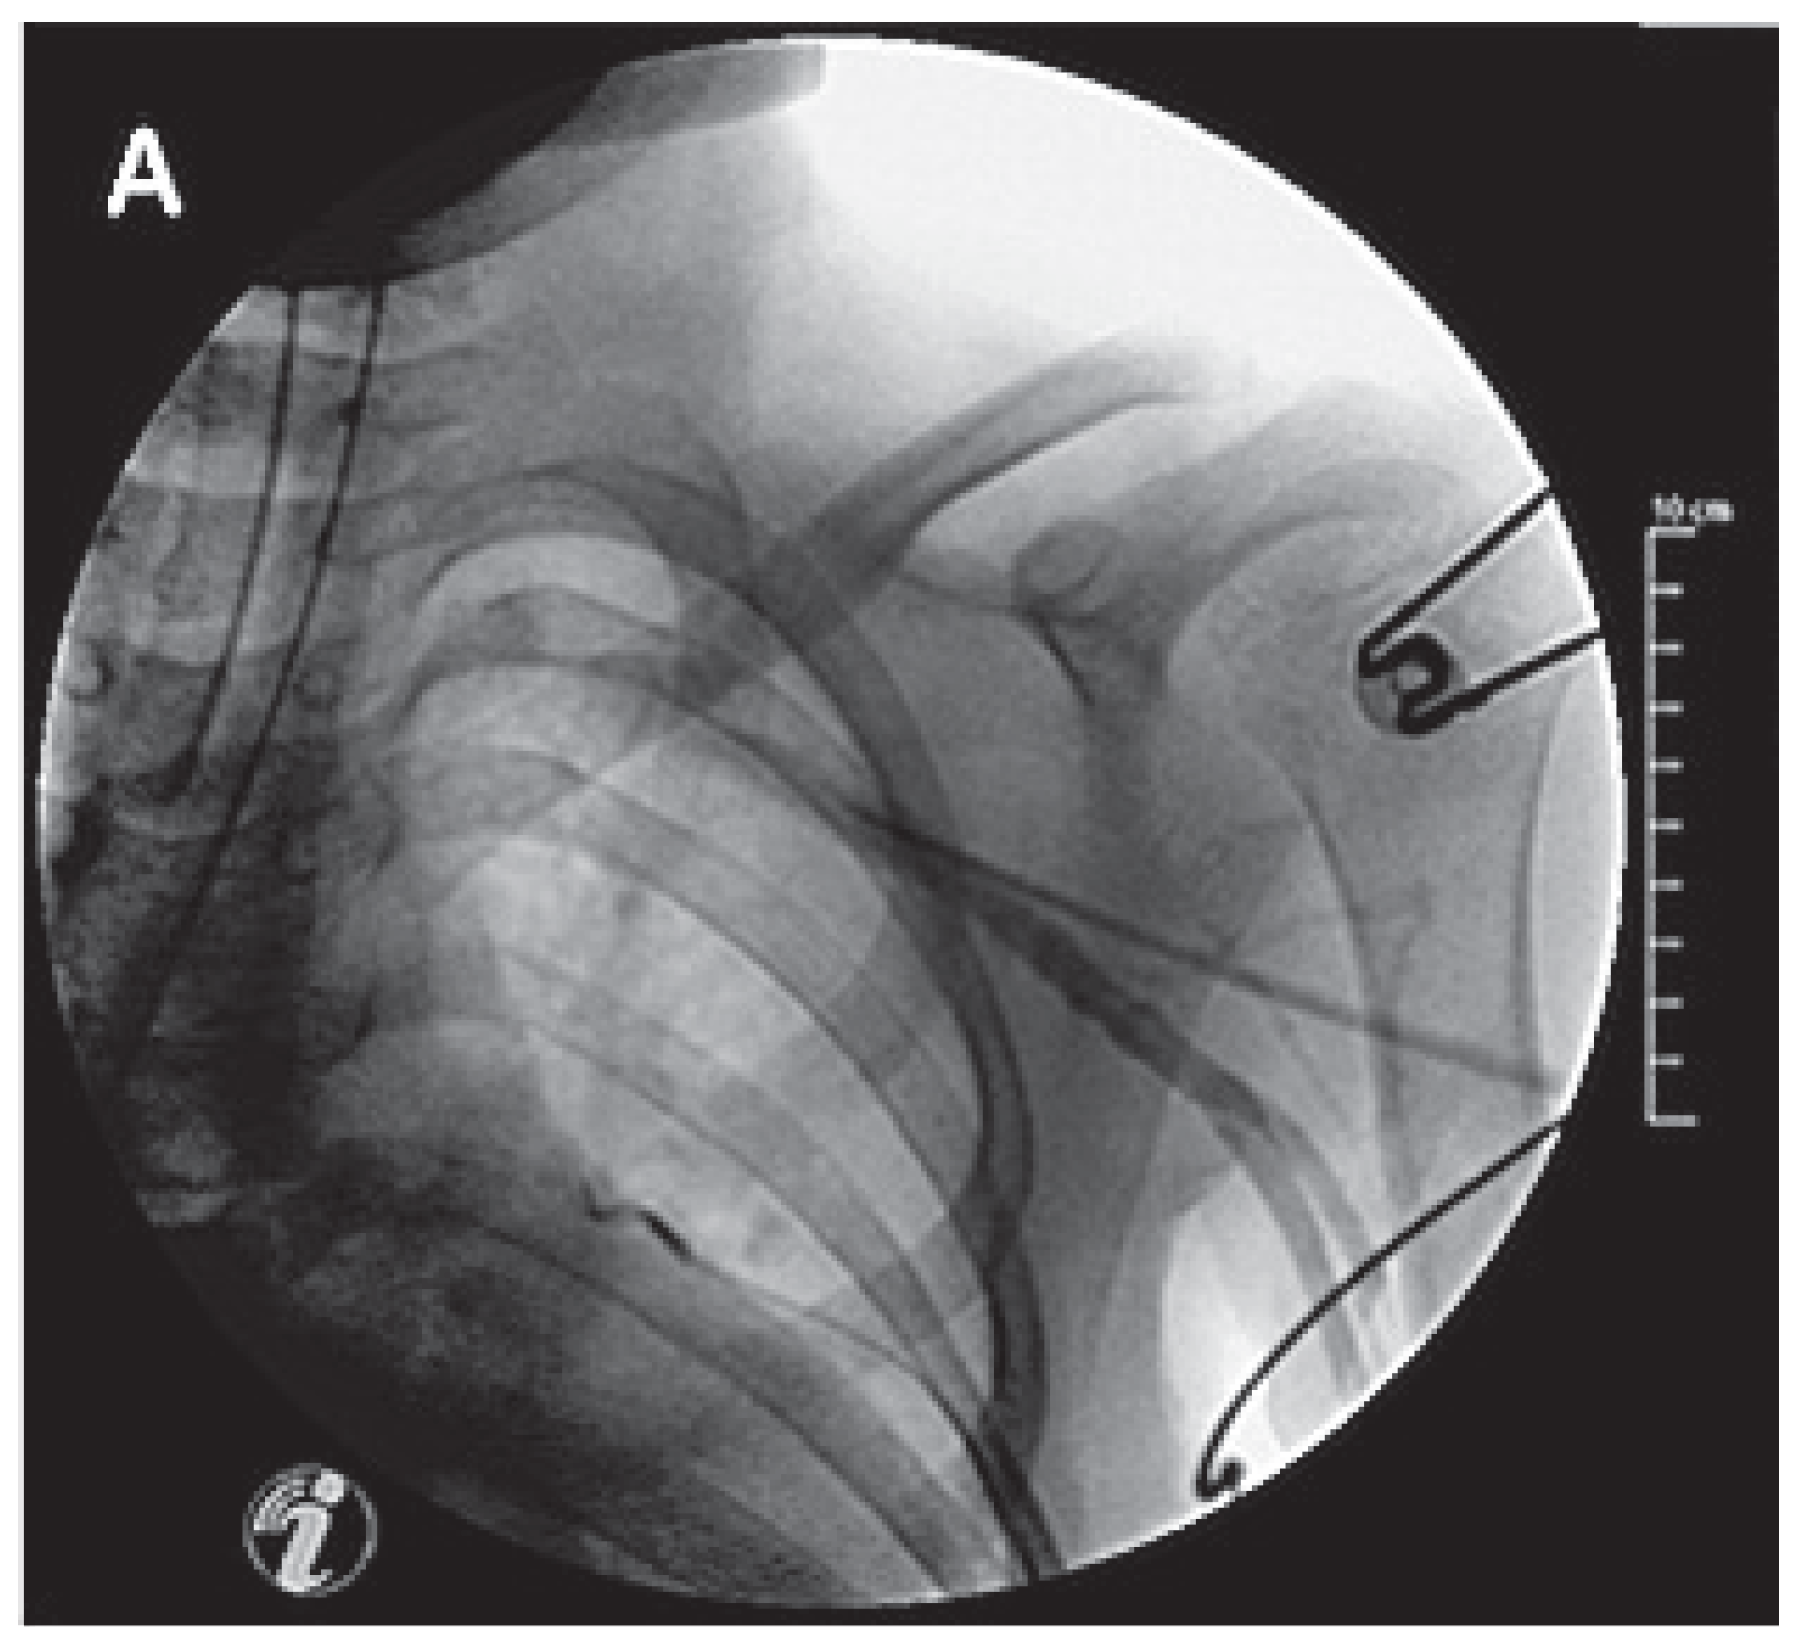

All procedures were performed under general anaesthesia. An incision was made parallel and slightly medial to the deltopectoral groove, with blunt dissection to the pectoralis major muscle and prepectoral (or retropectoral in the case of ICD implantation) pocket creation. The axillary vein was visualised under fluoroscopy by use of a bolus injection of 10 cc of semidiluted contrast via a venous catheter placed ipsilateral to the side of pacemaker implantation. The vein was punctured during the contrast injection by insertion of an 18G needle (a micropuncture kit was used in the patient with the lowest body weight) while connected to a 10 cc syringe half-filled with saline, under continuous aspiration. The puncture was performed during posteroanterior fluoroscopy (at 8 frames/s). The needle was aligned parallel to and overlying the opacified axillary vein before it was slowly advanced at an approximately 20°–30° angle through the pectoralis major muscle (Figure 1). The lower border of the first rib was sometimes reached with the needle (this marks the limit of the axillary vein and the extrathoracic subclavian vein), but care was taken never to cross the upper border of the first rib because of the risk of pneumothorax. Slight blanching of the opacified vein at the needle-tip heralded puncture of the vein, which was sometimes traversed, with aspiration of blood during careful withdrawal of the needle. As soon as a small quantity of blood was freely aspirated, a 0.035” J-wire was inserted into the axillary vein down to the inferior vena cava. In all but one case with multiple leads, separate punctures were performed under fluoroscopy, using the first guidewire as a landmark (a single puncture for introducing two leads was used, owing to the difficulty of accessing the axillary vein by means of a second stick after the first puncture).

Figure 1. Contrast-guided axillary vein puncture. Note that the needle is aimed coaxially with the vein (downstream to the needle tip).